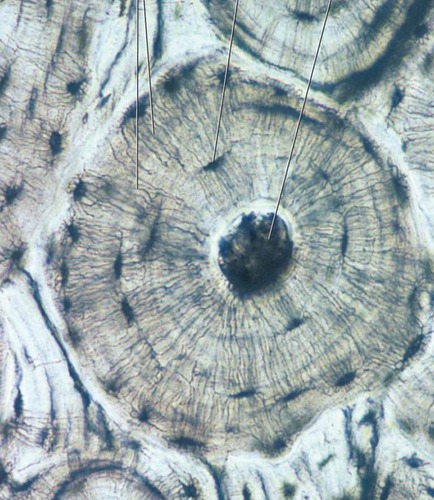

bone

support, protection, movement, forms blood cells, stores and releases inorganic chemicals